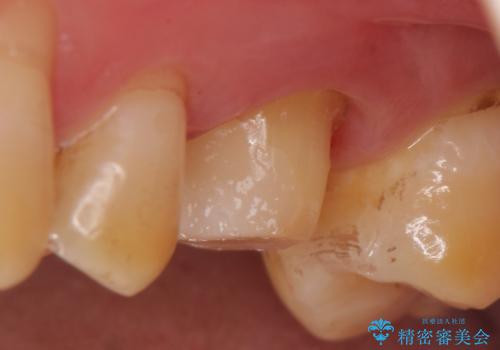

- ものを咬むと左上の奥歯が痛むので診て欲しいといらっしゃった方の症例です。

診査の結果、左上6が失活(歯の神経が死んでいる状態)しており根尖病変を認めたため、根管治療を行いました。

根尖病変の縮小及び症状の消失を確認後、オールセラミッククラウンによる補綴を行いました。